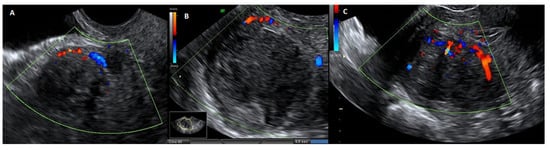

The abdominal myomectomy is a type of invasive surgery that can be performed robotically, laparoscopically or traditionally, by laparotomy. The first myomectomy was performed by Washington and John Atlee in 1844, and it has since established itself as the standard operation when the preservation of fertility and the uterus is considered vital []. Nevertheless, excessive bleeding, pyrexia, visceral injury, thrombosis, conversion to hysterectomy, blood transfusions, scar dehiscence in subsequent pregnancies, and several other intraoperative and postoperative problems are linked to abdominal myomectomy (Figure 1).

Figure 1.

Image of traditional laparotomic myomectomy on the left and removed fibroid on the right.